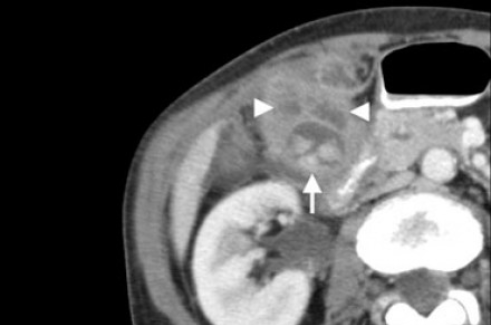

Острый калькулезный холецистит. После контрастного усиления визуализируется растянутый желчный пузырь (белые наконечники) со слегка утолщенной стенкой. Визуализируется камень в шейки желчного пузыря (белая стрелка).